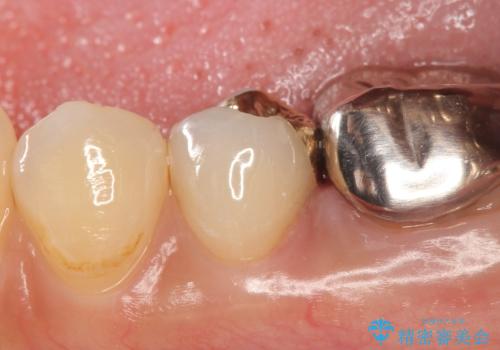

- 右下5番目の歯がしみるといらっしゃった方の症例です。

銀歯及び虫歯を除去し、適合に優れたPGA(ゴールド)インレーにて修復を行いました。

ゴールドは化学的な安定性が高いため変色や腐食がほとんどなく、アレルギーなども起こりにくい人体に優しい素材です。

また硬さも天然歯に近いため周囲の歯への影響も少なく、さらに適合もよいため虫歯の再発も少ない、とても補綴に適した材料です。